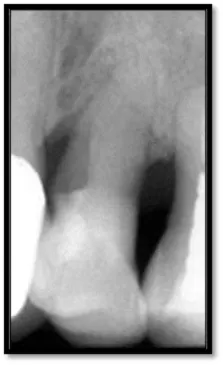

As you can see, calculus is visible on the mesial surfaces of both molars and the extent of bone loss mesial of # 30 is significant. 18 months post treatment:

Pocket depths are now 2-5mm (above left), Notice the nice bone fill on the mesial of both molars (above right)